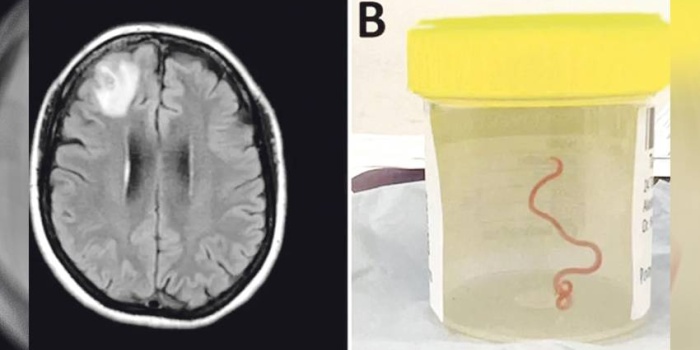

Li paytexta Awustralyayê, Canberrayê bûyerek qewimî ku heta îro di dîroka tibê de nehatibû dîtin. Cerahê mejî li nexweşxaneya Canberrayê, Harî Priya Bandî, ji mejiyê jinekê kurmekî 8 santîmetreyan dirêj derdixe. Ew bi telefonê ji pisporê nexweşiyên ji ber înfeksiyonê yê li heman nexweşxaneyê, Dr. Sanjaya Senanayake re dibêje, “Xwedêwo! Min beriya bi çendekî di mejiyê vê jinê de kurmek dît, zindî ye û nasekine!”

Kurmî ji pisporekî re dişînin û ew jî ecêbmayî dibêje, “Ev Ophidascaris roberts e.” Yanî bi vê bûyerê re, ev cara pêşî ye ku ev parazît li cem mirovan hatiye dîtin. Ji ber ku jina 64 salî nêzî golekê giya û pincar kom dikirin û li wir pîton jî gelek in, li gorî texmînan vî kurmê parazît ji van pincar û gihayan vegirtiye wê.